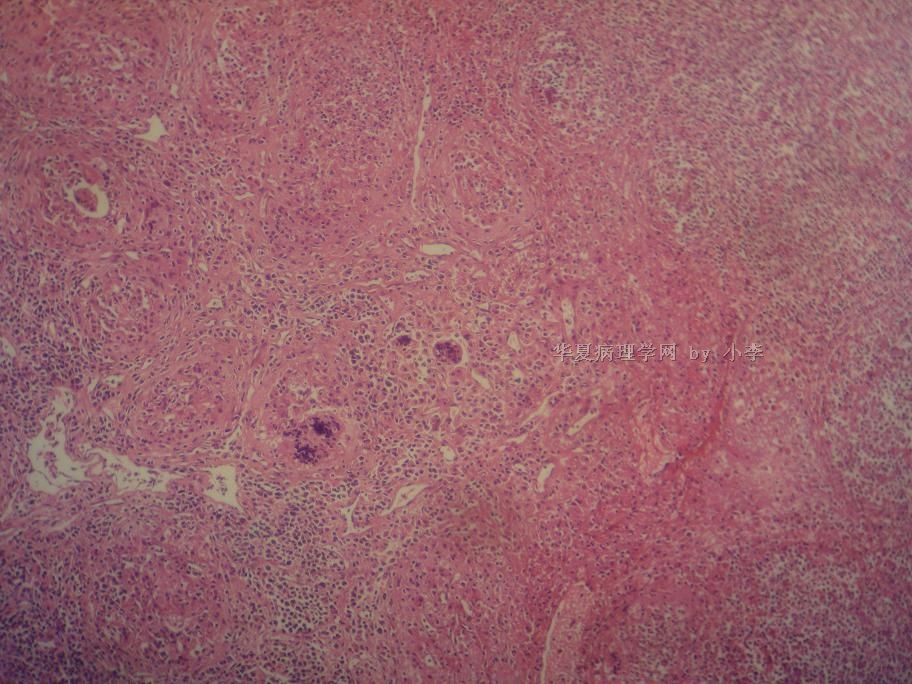

睾丸炎?

• 睾丸炎?图1

图1

首先考虑精子肉芽肿

肉芽肿性睾丸炎

精子肉芽肿